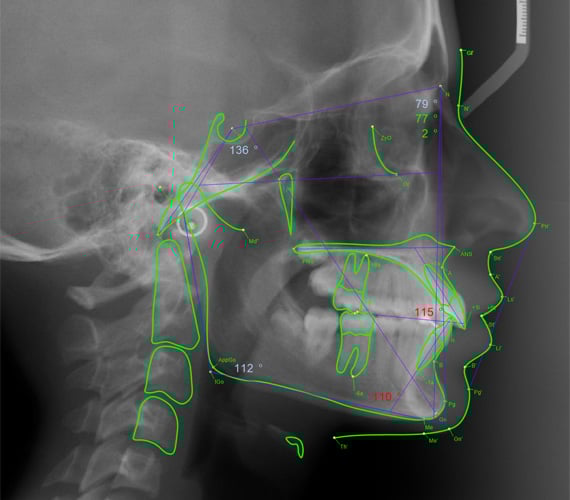

Les analyses céphalométriques peuvent être réalisées de deux manières :

- Tracé manuel sur papier transparent à partir du cliché radiographique

- Analyse informatisée grâce à des logiciels spécialisés

Notions Fondamentales : Points, Lignes et Plans

Définitions Essentielles

Point anatomique : Correspond à un repère anatomique précis et visible sur la radiographie (exemples : Nasion, Épine Nasale Antérieure).

Point défini : Ne correspond pas à un point anatomique visible mais doit être précisé sur une région squelettique, cutanée ou dentaire (exemples : Point A de Downs, Point B).

Point construit : Nécessite une construction géométrique pour être déterminé (exemple : Point Xi, centre de la branche montante).

Ligne : Définie par deux points reliés entre eux.

Plan : Défini par trois points non alignés.

Plan de référence : Plan sélectionné comme base pour effectuer des mensurations linéaires ou angulaires (exemple : Plan Horizontal de Francfort).

Analyse Céphalométrique Informatisée

L’informatisation de la céphalométrie a révolutionné la pratique orthodontique moderne. Les logiciels spécialisés offrent :

- Rapidité d’exécution : Le tracé et les mesures sont réalisés en quelques minutes contre 30 à 45 minutes pour un tracé manuel.

- Précision accrue : Élimination des erreurs de mesure et de calcul humaines.